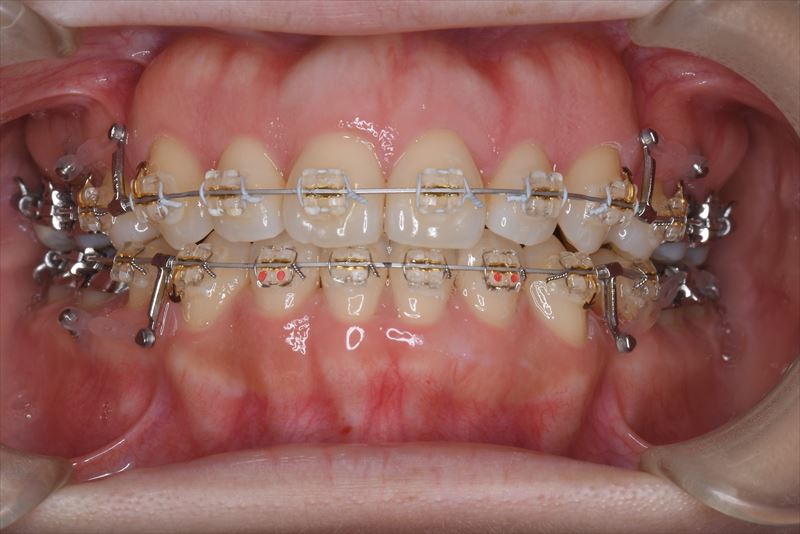

治療中

マルチブラケット装置、アンカースクリュー

上顎両側4番抜歯、下顎両側4番抜歯、下顎両側8番抜歯